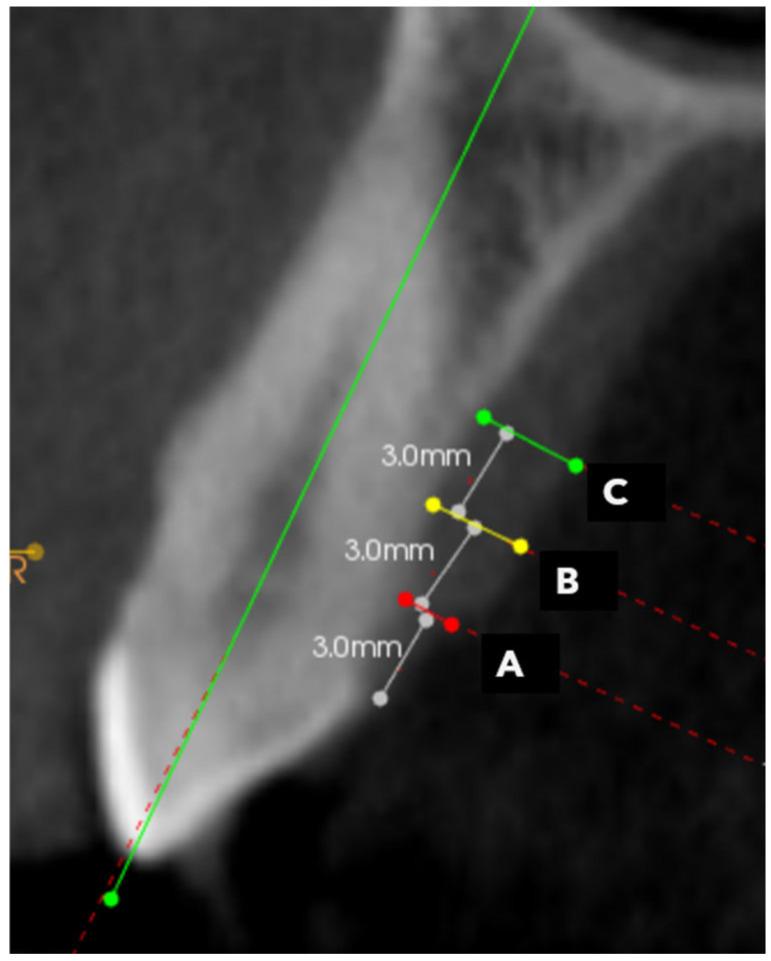

Periodontal and implant therapies frequently require soft tissue augmentation for optimal outcomes. As the hard palate serves as the primary donor site, this study evaluated palatal masticatory mucosa thickness variations in a Saudi population of the Eastern Province using cone-beam computed tomography (CBCT) at a teaching dental hospital, providing site-specific data for clinical applications. A retrospective cross-sectional analysis of 215 CBCT scans from systemically healthy, non-smoking adults (>18 years) was conducted at the University Dental Hospital. Measurements were taken at 12 standardized sites (3 mm, 6 mm, and 9 mm from the cementoenamel junction) across maxillary canines, premolars, and first molars. Statistical analysis included Friedman's test and t-tests. Significant site variations were observed, with the second premolar region showing greatest thickness (3.48 ± 0.80 mm at 9 mm) and the first molar region the lowest (1.88 ± 0.63 mm at 3 mm) ( < 0.001). Mucosal thickness generally increased coronally to apically ( < 0.001). Age >35 years correlated with significantly thicker mucosa ( < 0.05), while no statistically significant gender-based differences were observed for all sites ( > 0.05). CBCT provides reliable, non-invasive assessment of palatal mucosa thickness. These findings offer region-specific data for consideration in periodontal and implant procedures involving soft tissue grafting.

牙周治疗和种植治疗常常需要进行软组织增量术以获得最佳疗效。由于硬腭是主要的供区,本研究在一家教学型牙科医院,使用锥形束计算机断层扫描(CBCT)评估了沙特东部省份人群的腭部咀嚼黏膜厚度变化,为临床应用提供了特定部位的数据。在大学牙科医院对215例来自全身健康、不吸烟的成年人(>18岁)的CBCT扫描进行了回顾性横断面分析。在上颌尖牙、前磨牙和第一磨牙的12个标准化部位(距牙骨质釉质界3 mm、6 mm和9 mm)进行测量。统计分析包括弗里德曼检验和t检验。观察到显著的部位差异,第二前磨牙区域显示出最厚的厚度(9 mm处为3.48±0.80 mm),第一磨牙区域最薄(3 mm处为1.88±0.63 mm)(<0.001)。黏膜厚度通常从冠部到根部逐渐增加(<0.001)。年龄>35岁与黏膜明显增厚相关(<0.05),而所有部位均未观察到基于性别的统计学显著差异(>0.05)。CBCT提供了对腭黏膜厚度可靠的、非侵入性的评估。这些发现为涉及软组织移植的牙周和种植手术提供了特定区域的数据以供参考。